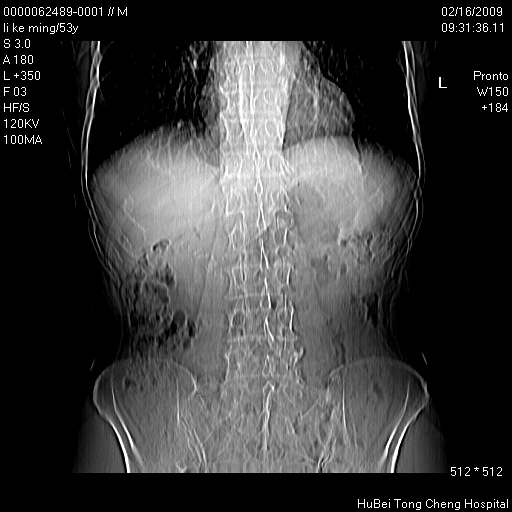

以下是引用卜一在2009-2-16 16:13:00的发言:[br]胰胆管扩张,末端明显狭窄 梗阻,胰头及十二指降段壶腹部结构紊乱。多考虑:十二指降段壶腹部癌!

以下是引用zsl6918在2009-2-17 8:48:00的发言:[br]符合胰头癌侵犯十二指肠。